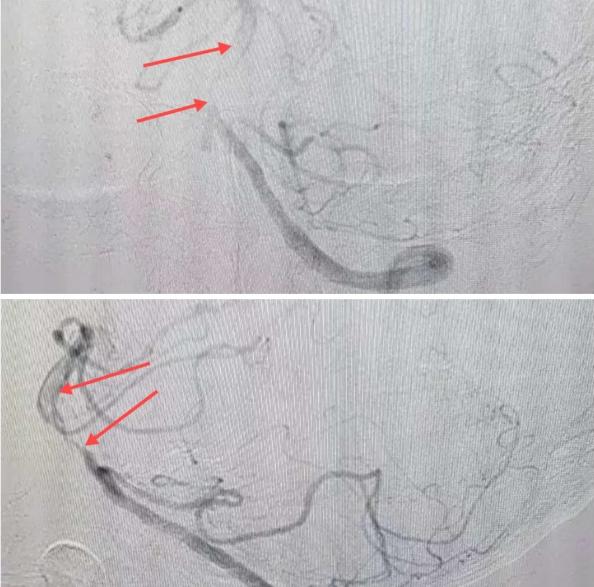

磁共振MRA提示基底動(dòng)脈閉塞

造影可見血管夾層和大量血栓形成